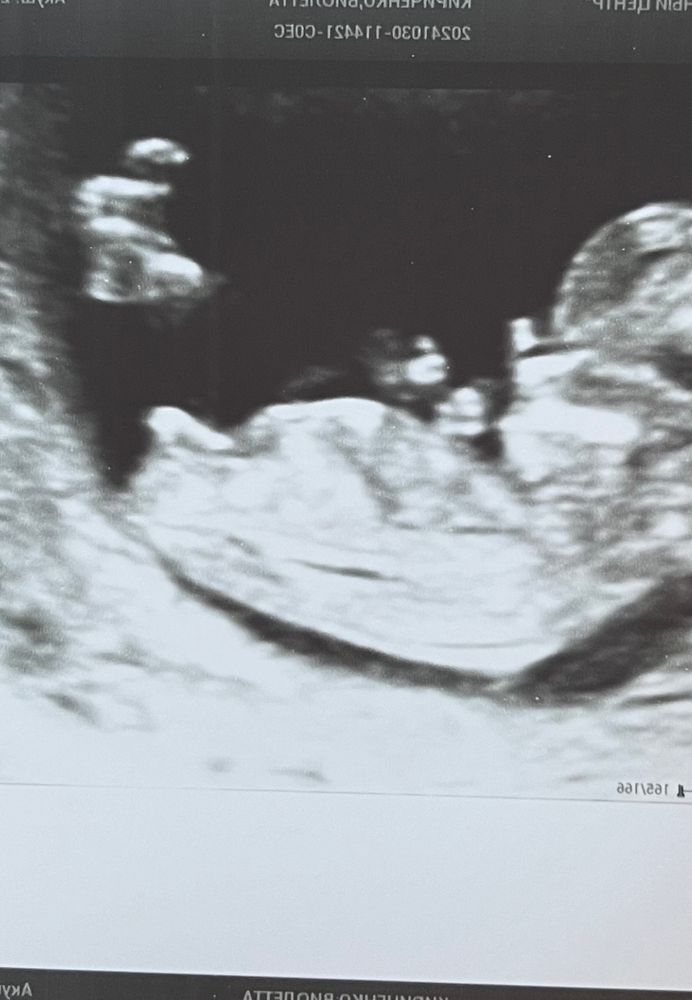

GinBerry, Интересно,не подскажите , а у меня кто? 😅 Может угадаете) Изображение Изображение

Виолетта Кириченко, как у Вас тоже хорошо видно) больше похоже, что бугорок параллельно спинке, что указывает на девочку. У мальчика он вверх смотрит) хотя у Вас он чуть чуть вздернут вверх из-за чего я бы допустила процентов 20 на мальчика 😁 У меня прям ровно по спинке )

29.11.2024